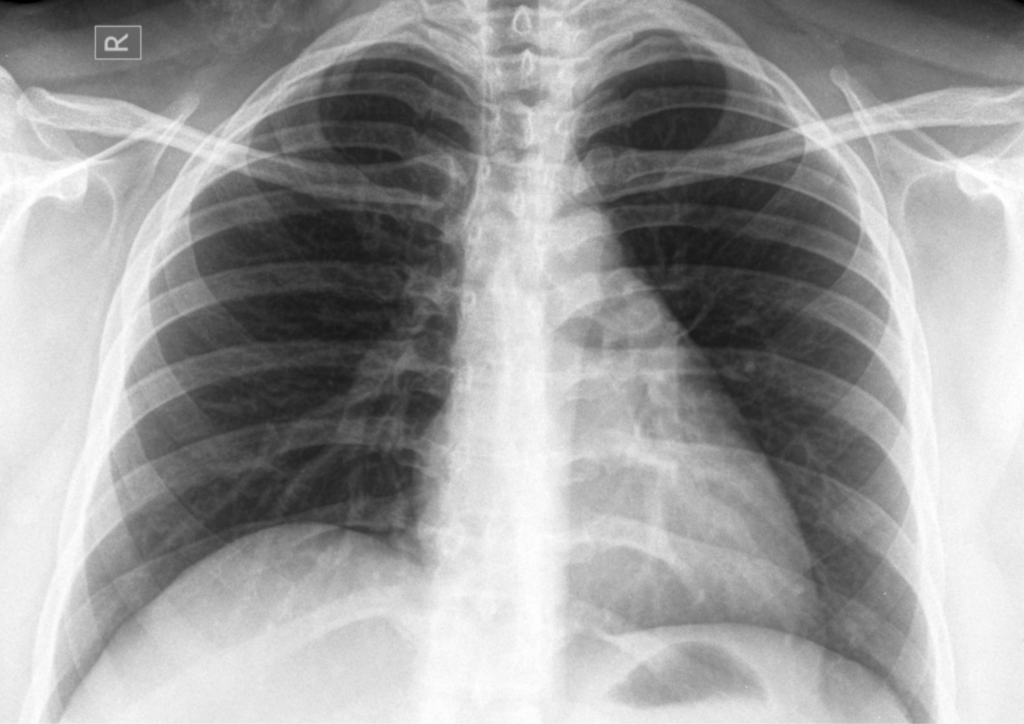

肺炎の診断結果